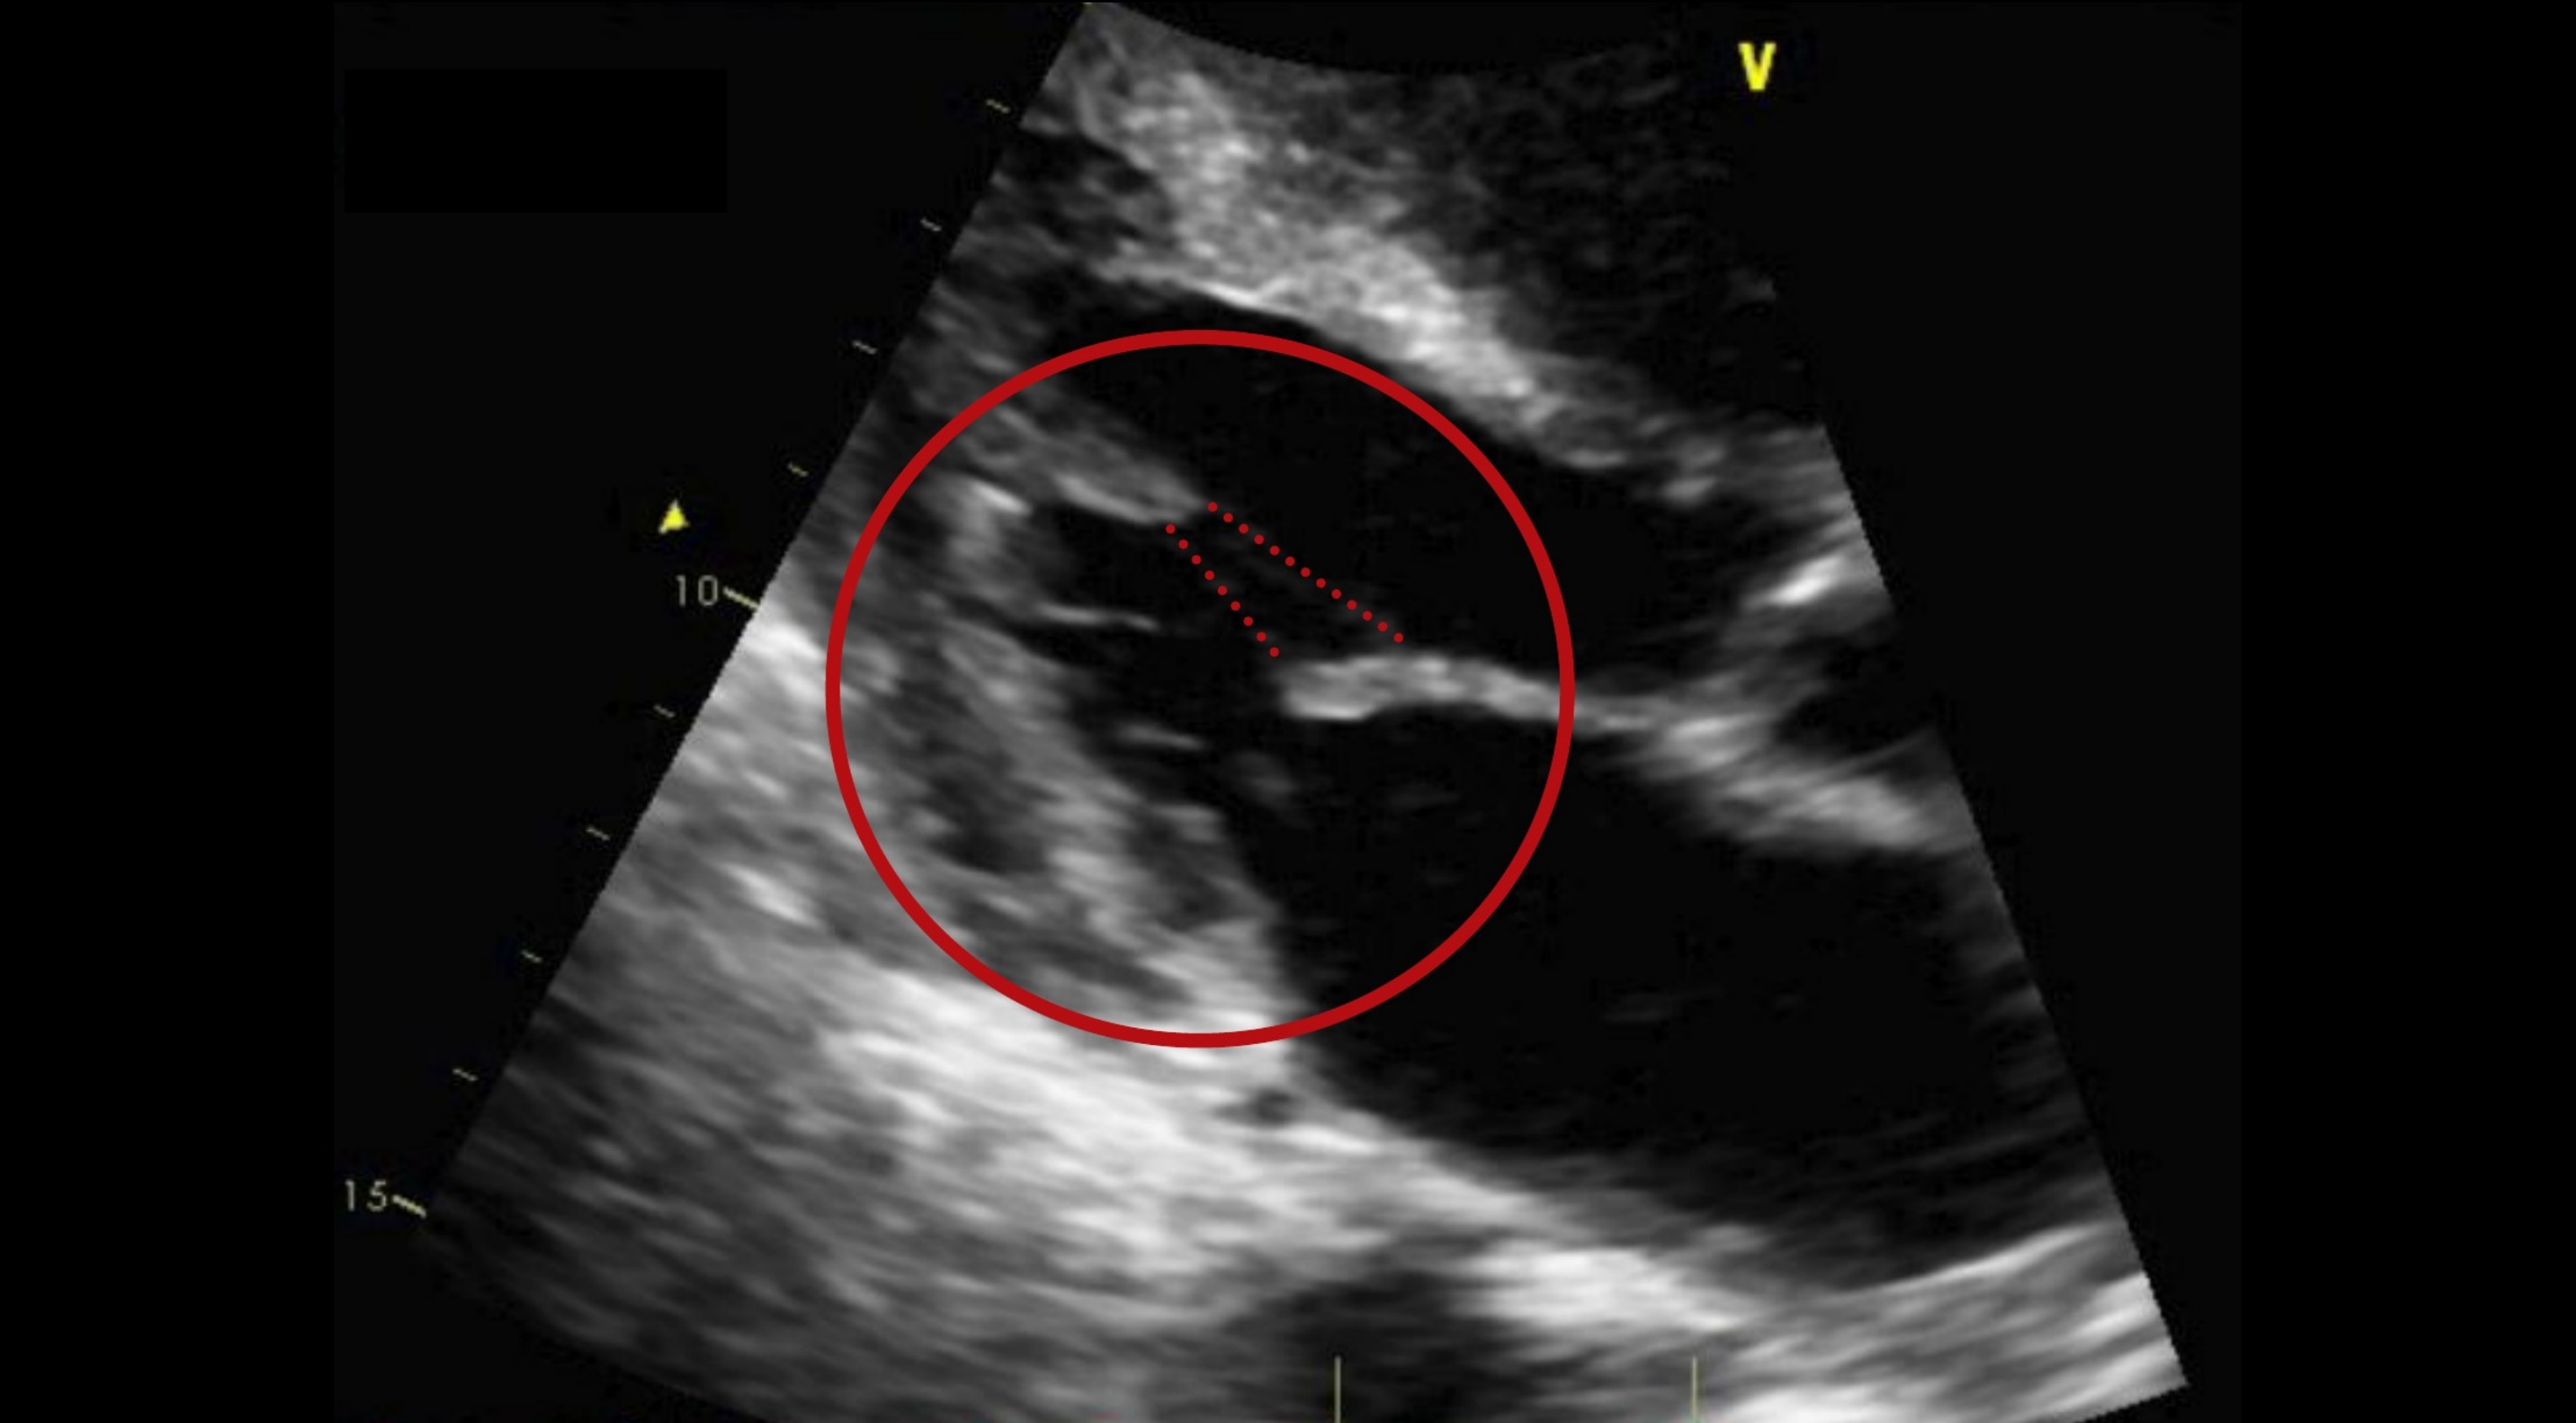

Systolic anterior motion of the mitral valve as seen by... Download Scientific Diagram Mitral Valve Anatomy Echo mitral valve has historically been a structure of interest by pioneers in echocardiography. technical advances have enabled echocardiography to identify almost any anatomic or functional abnormality of. The main mitral valve apparatus components are (1) mitral annulus, (2) mitral valve leaflets, (3) chordae tendineae, and (4) papillary muscles. mitral regurgitation (mr) is one of the most common. Mitral Valve Anatomy Echo.